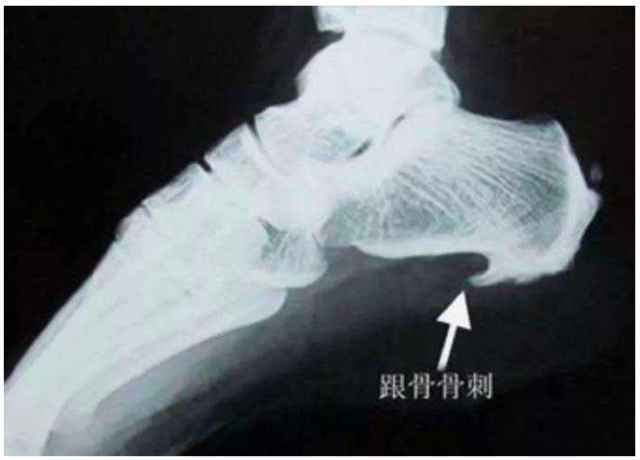

跟骨骨刺图片

跟骨骨刺图片,正常人右跟骨图片

跟骨骨刺x线图片

足跟骨刺图片

跟骨骨刺

脚后跟骨刺图片